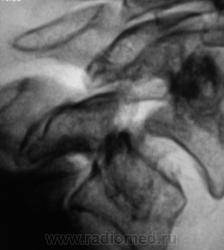

Ребята выпили, закусили, еще раз и еще раз. Потом хозяин вспомнил, что поспели груши... и полез на грушу. Поли привиделось что-то, толи вспомнил, как прыгал с парашюта, но соизволил спикировать..., шею и заклинило...

Двусторонний скользящий подвывих С5, с одной стороны верховой.

Вы правы.